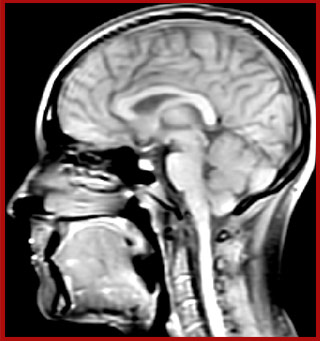

T1 - weighted

Myelin water imaging (echo 1)

T1 - Weighted, Myelin Water Fraction Superimposed

Spinal cord coverage

Smaller, more isotropic voxels

Excellent detail in quantitative maps

Images courtesy of Adam Dvorak, Department of Physics and Astronomy, University of British Columbia